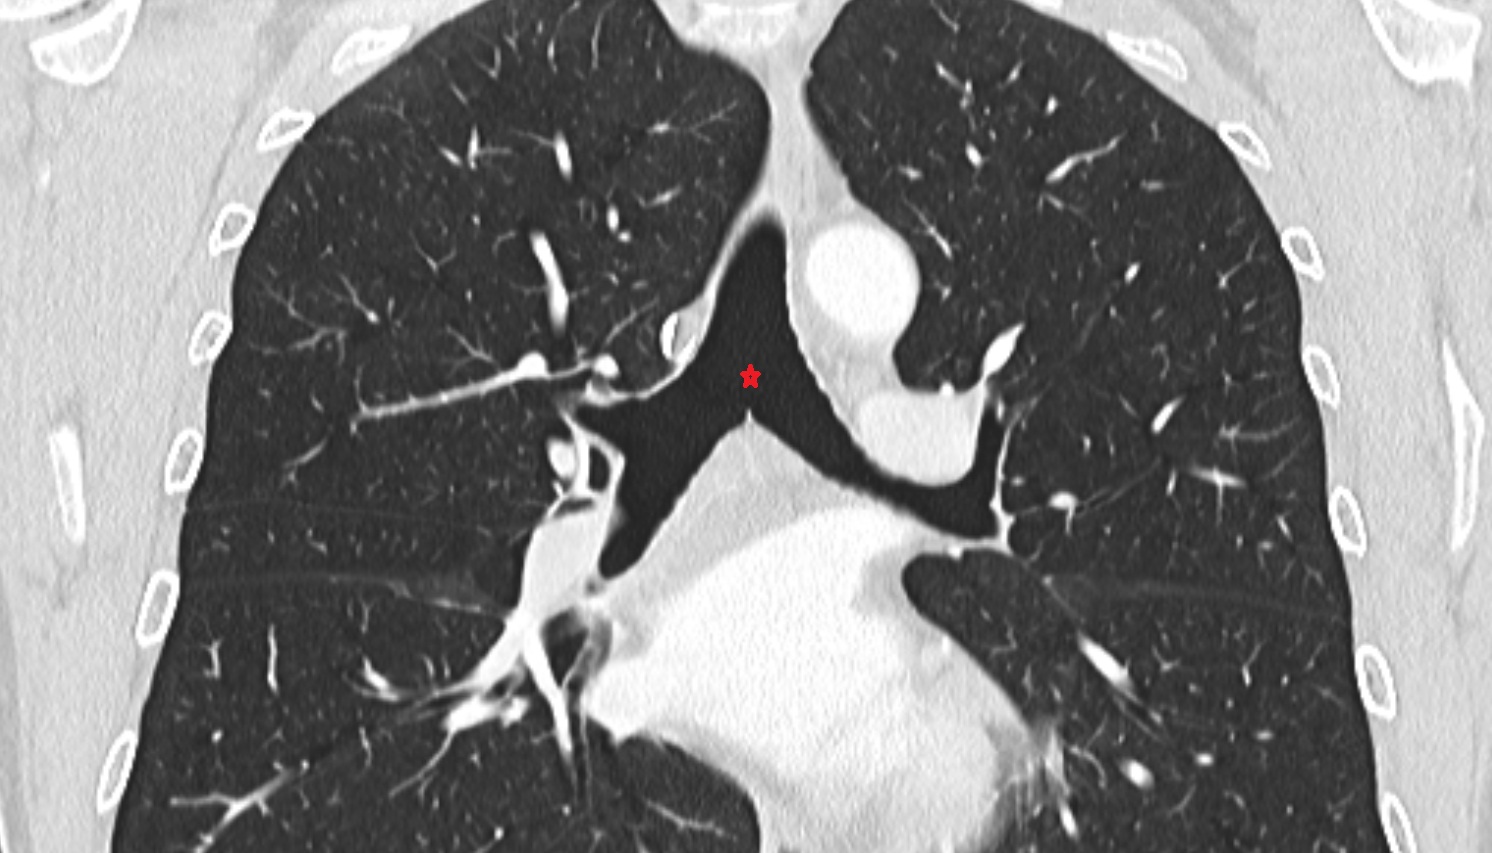

- Right main bronchus

- Left main bronchus

- Right lung (superior lobe)

- Right lung (middle lobe)

- Right lung (inferior lobe)

- Left Lung (Superior Lobe)

- Left lung (inferior lobe)

- Oblique fissure of left lung

- Oblique fissure of right lung

- Horizontal fissure of right lung